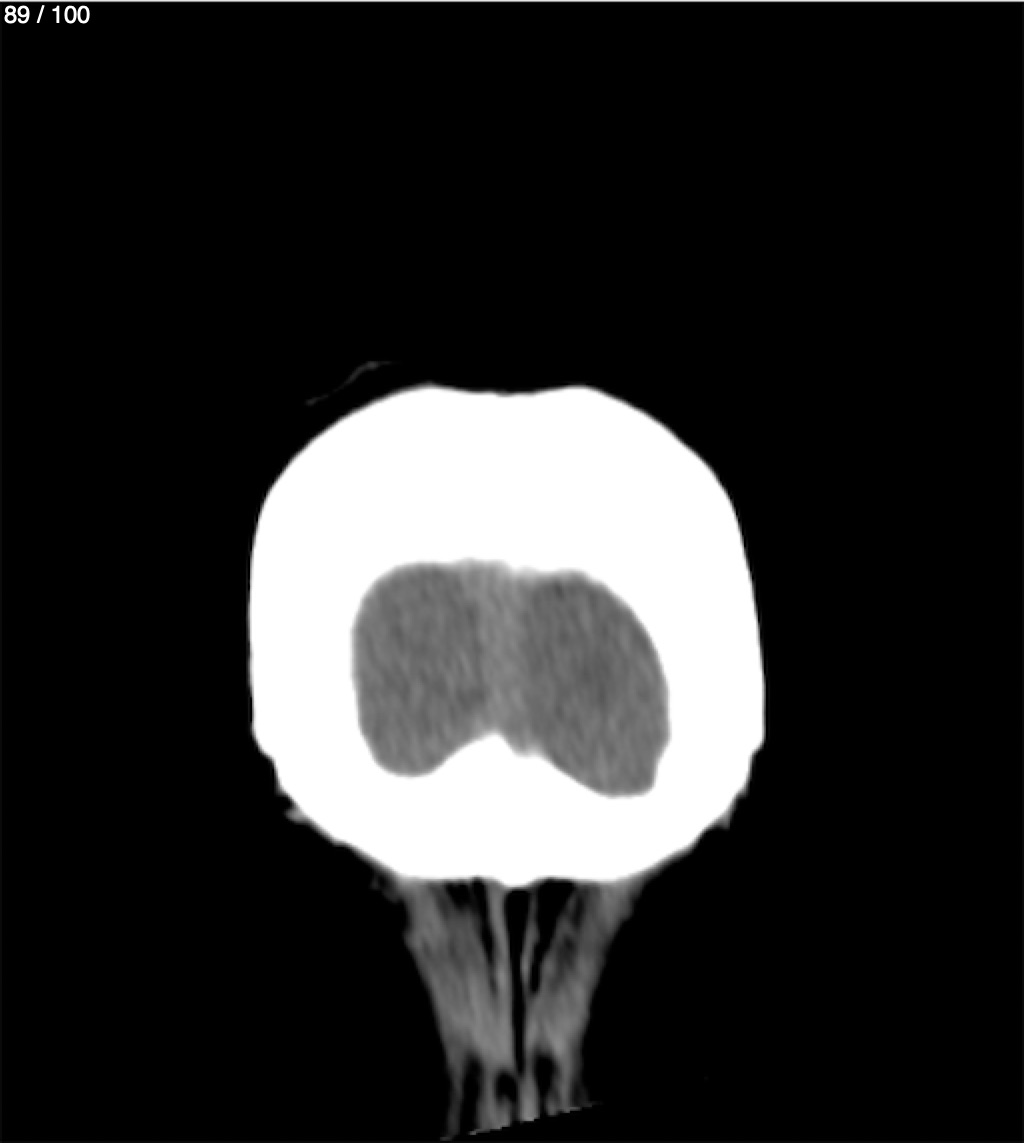

Jose Sosa Martinez 66A - Angiotac Craneo